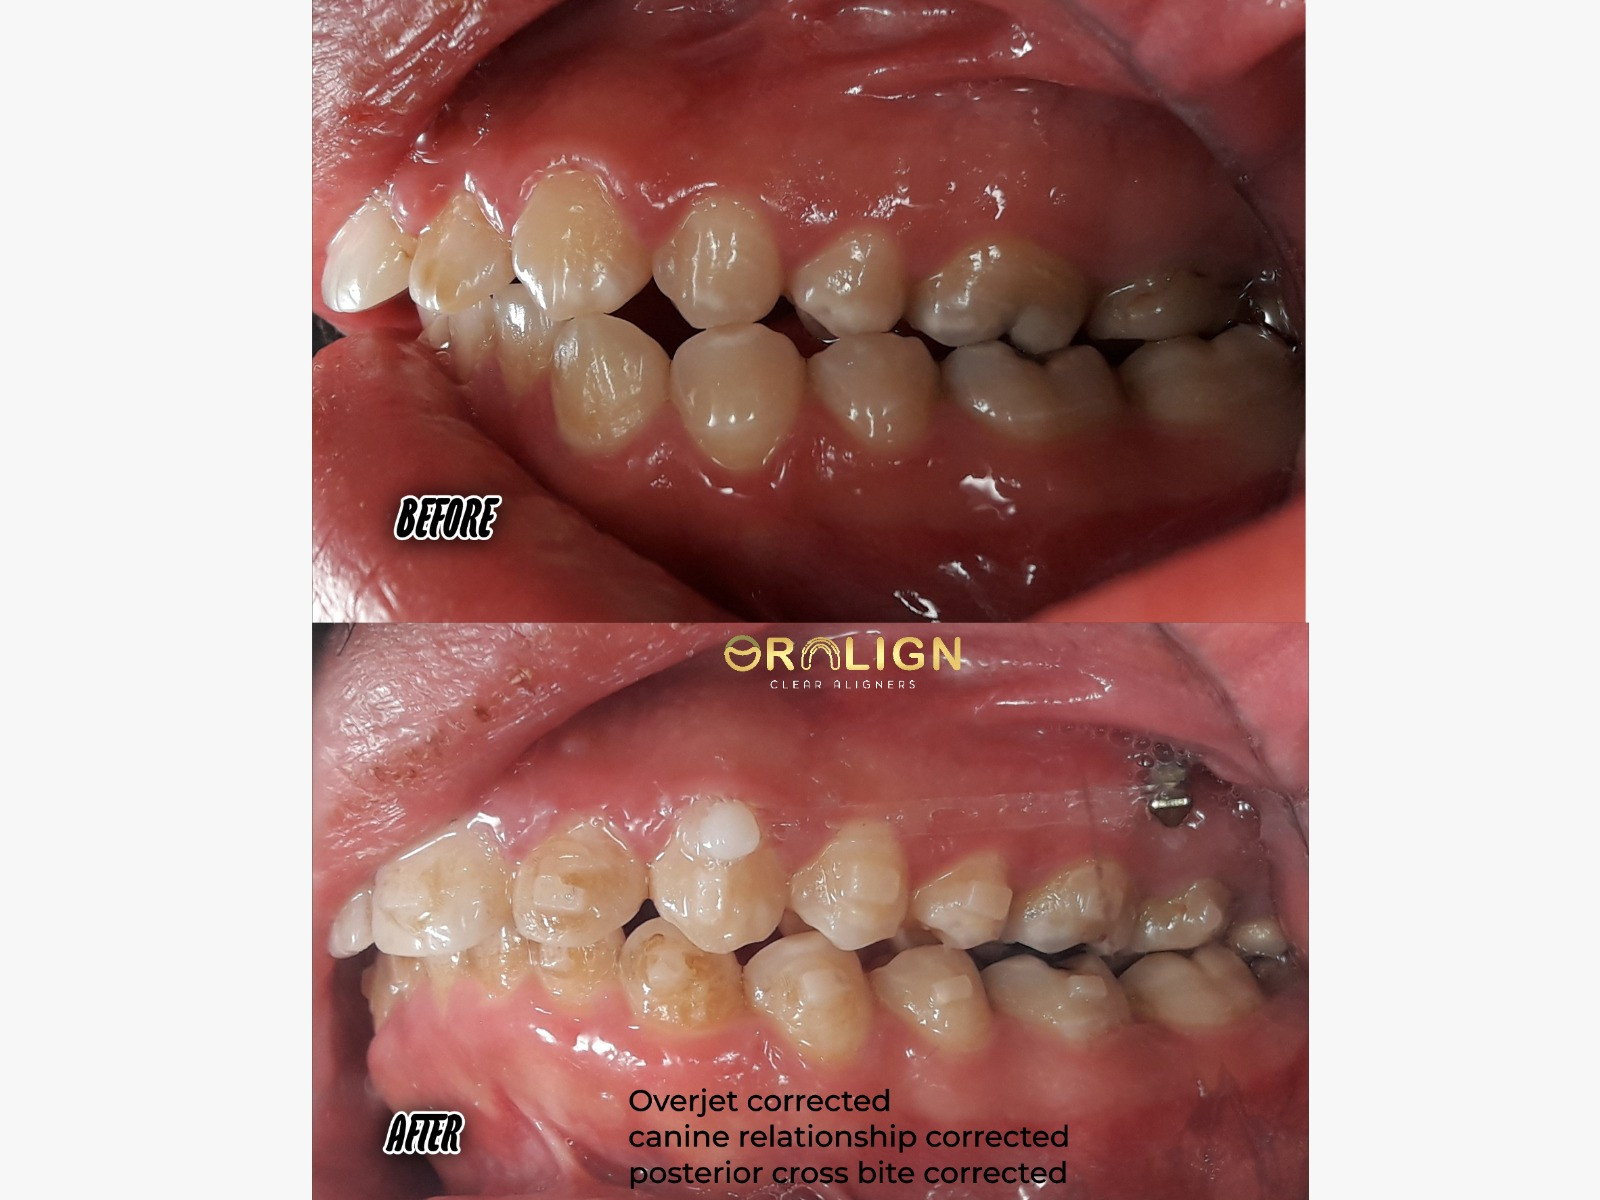

نتائج موثوقة

استعد ثقتك من جديد

شاهد نتائج حقيقية مع آلاف الحالات الناجحة التي حققنا معها المستحيل.